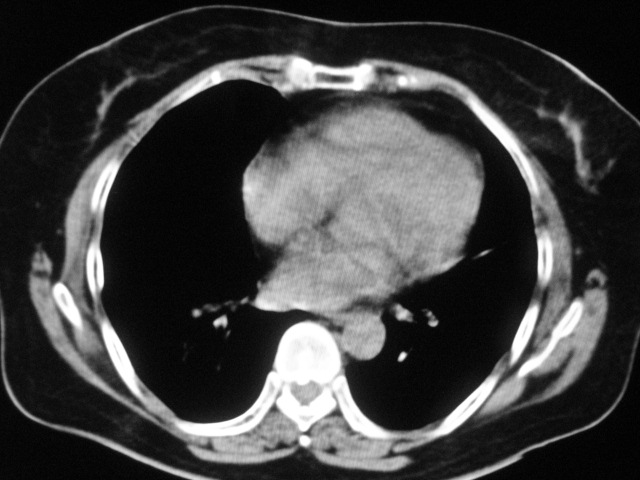

以下是引用天南地北在2007-8-27 23:49:00的发言:[br]右肺下叶可见斑片状高密度影,边缘模糊;右肺中叶内侧段及左肺舌段亦可见小斑片状模糊影。[br]考虑双肺感染,建议积极抗炎治疗后复查。

以下是引用难听在2007-8-28 13:17:00的发言:[br]右肺下叶背段支气管狭窄,是否可以考虑新生物伴阻塞性肺炎.请大家帮帮忙,这个病人是卫生局长的丈母娘.惹不起啊.